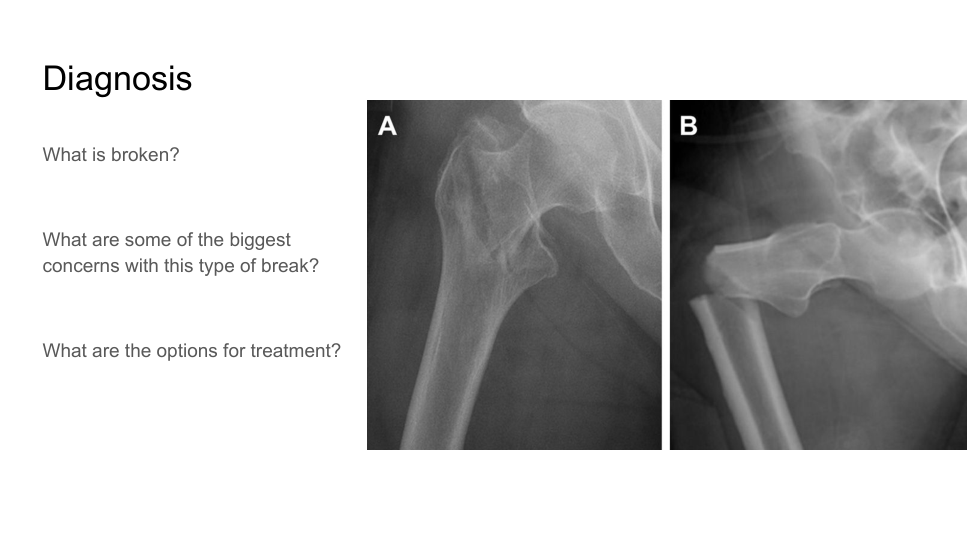

what structure is broken?